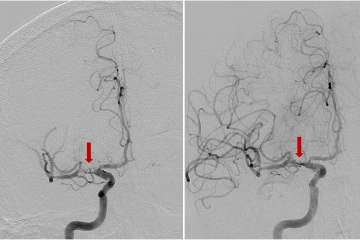

Moyamoya disease typically affects young people, even children, who are seemingly healthy until the condition is discovered following a stroke. After a stroke, moyamoya patients often “sit at a tipping point,” says Dr. Wang. “They have the potential both for an excellent recovery or for disastrous progression.” To better ensure that a patient tips toward recovery, researchers at UCLA are testing non-invasive interventions to protect vulnerable regions of the brain adjacent to the initial stroke. For instance, stimulation of certain nuclei using high-intensity focused ultrasound appears to have a neuroprotective effect. Transcranial direct-current stimulation is currently in trials for patients with acute strokes caused by large vessel occlusion, and may prove useful for moyamoya patients as well.

With an arteriovenous malformation, treatment decisions are nuanced and depend on whether the vessel has caused bleeding in the brain or not, says neurosurgeon Jeremiah Johnson, MD. “These complex tangles of blood vessels in the brain can rupture and cause hemorrhagic stroke,” explains Dr. Johnson. “The definitive treatment is surgery to remove the malformation, but sometimes that’s not possible due to location in the brain or other factors. For very deep or critical parts of the brain, for example, we often avoid surgery but may be able to treat with other modalities.”

If the blood vessel malformation hasn’t ruptured, ongoing monitoring can sometimes be the safest option, but each patient and each malformation is different. The preferred option to treat some AVMs may be stereotactic radiation, where radiation beams are tightly focused on the malformation but minimally impacting the surrounding normal tissues. Or it could involve embolization, or blocking off surrounding branches of the blood vessel to safely remove the malformation. UCLA provides individualized expert care for even the most complex cerebrovascular disorders. Both Dr. Johnson and Dr. Colby are dual-trained in endovascular and cerebrovascular open surgery techniques, with expertise to perform these multifaceted procedures.